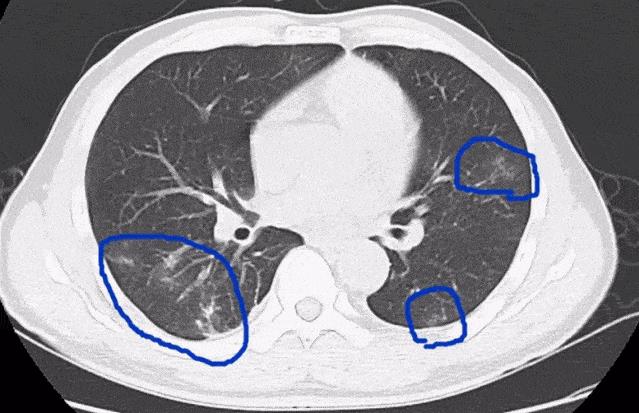

左:驅(qū)蟲前,右:驅(qū)蟲后

寄生蟲侵入肺部 圖源/網(wǎng)絡(luò)